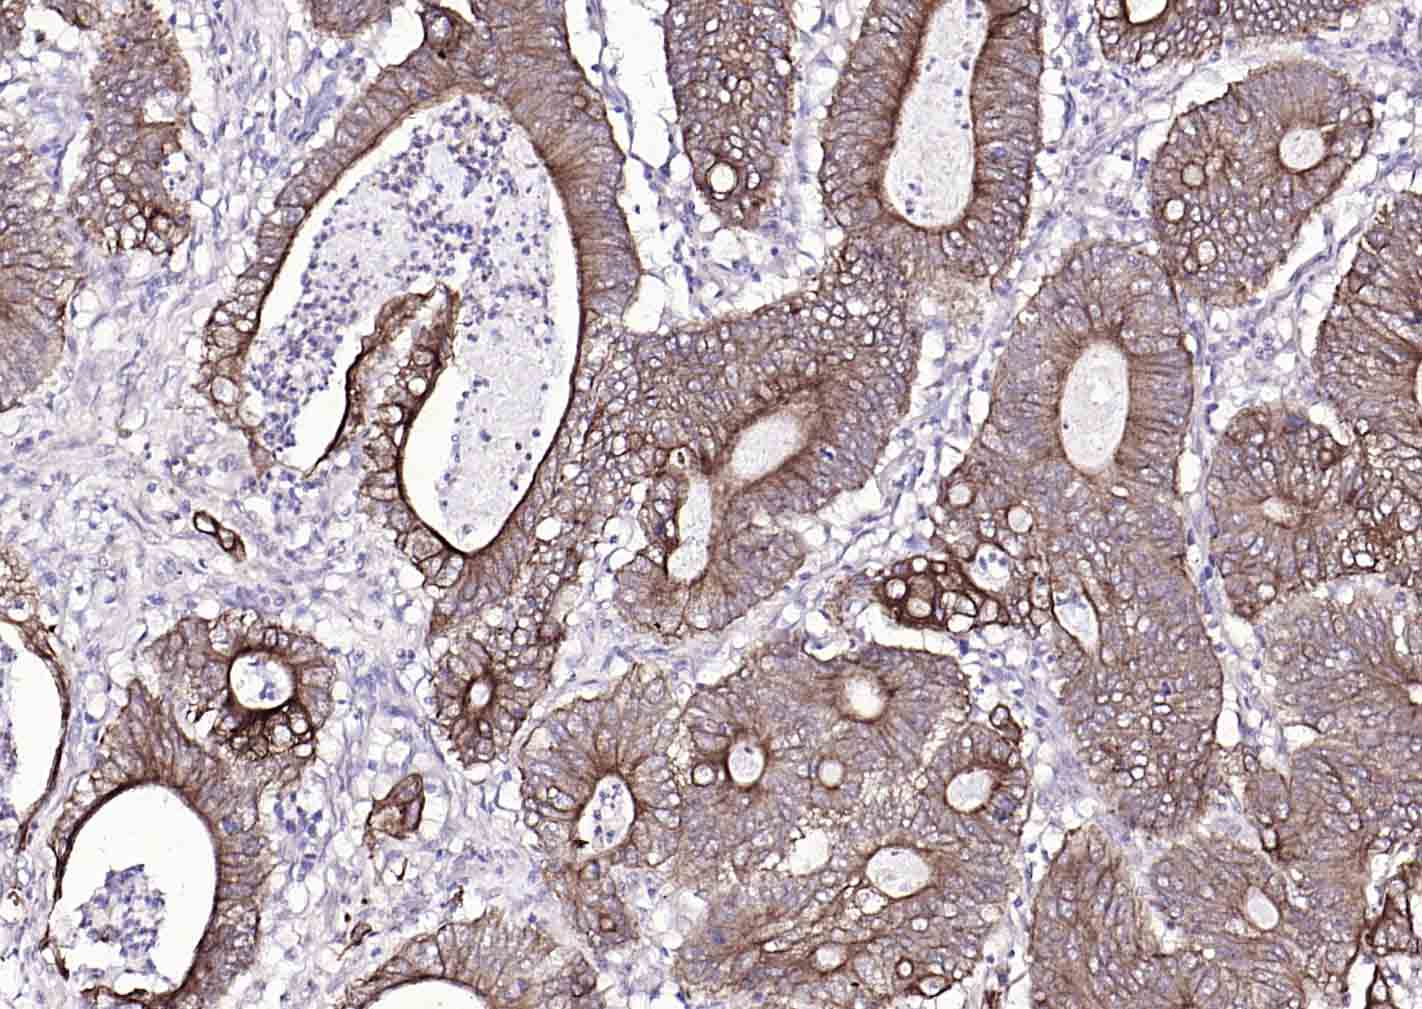

P-CK广谱细胞角蛋白(AE1/AE3)主要标记角化上皮、复层鳞状上皮、复层上皮、增生的角化上皮和单层上皮,用于鳞癌,各种腺癌 、移行上皮癌,小细胞癌,恶性间皮瘤、生殖细胞肿瘤,部分滑膜肉瘤、平滑肌肉瘤等表达。

广谱细胞角蛋白PCK单克隆抗体-bsm-34137M广谱细胞角蛋白PCK单克隆抗体-bsm-34137M广谱细胞角蛋白PCK单克隆抗体-bsm-34137M广谱细胞角蛋白PCK单克隆抗体-bsm-34137M广谱细胞角蛋白PCK单克隆抗体-bsm-34137M广谱细胞角蛋白PCK单克隆抗体-bsm-34137M广谱细胞角蛋白PCK单克隆抗体-bsm-34137M广谱细胞角蛋白PCK单克隆抗体-bsm-34137M广谱细胞角蛋白PCK单克隆抗体-bsm-34137M广谱细胞角蛋白PCK单克隆抗体-bsm-34137M广谱细胞角蛋白PCK单克隆抗体-bsm-34137M广谱细胞角蛋白PCK单克隆抗体-bsm-34137M广谱细胞角蛋白PCK单克隆抗体-bsm-34137M广谱细胞角蛋白PCK单克隆抗体-bsm-34137M广谱细胞角蛋白PCK单克隆抗体-bsm-34137M

IHC-PHuman, Mouse, Rat1:100-500